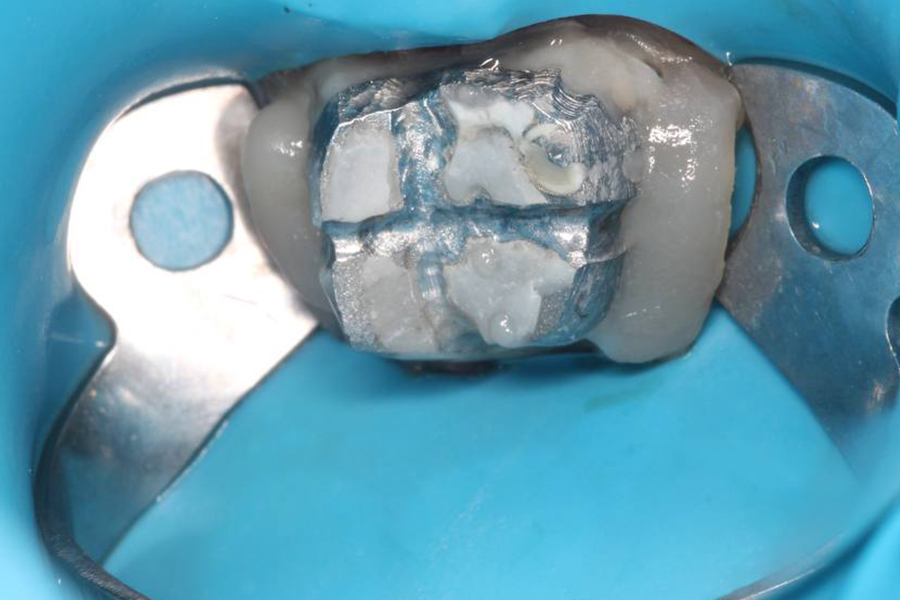

Использована туннельная техника — малотравматичный подход, при котором:

1. сохраняется кровоснабжение тканей,

2. нет вертикальных разрезов, такой подход обеспечивает предсказуемое заживление и высокую эстетичность результата без заметных рубцов.